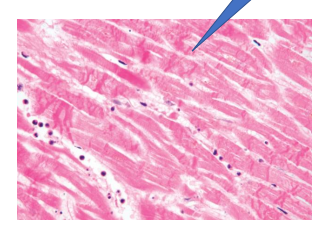

Myocardial infract early stages

Myocardial infract

green = early infract